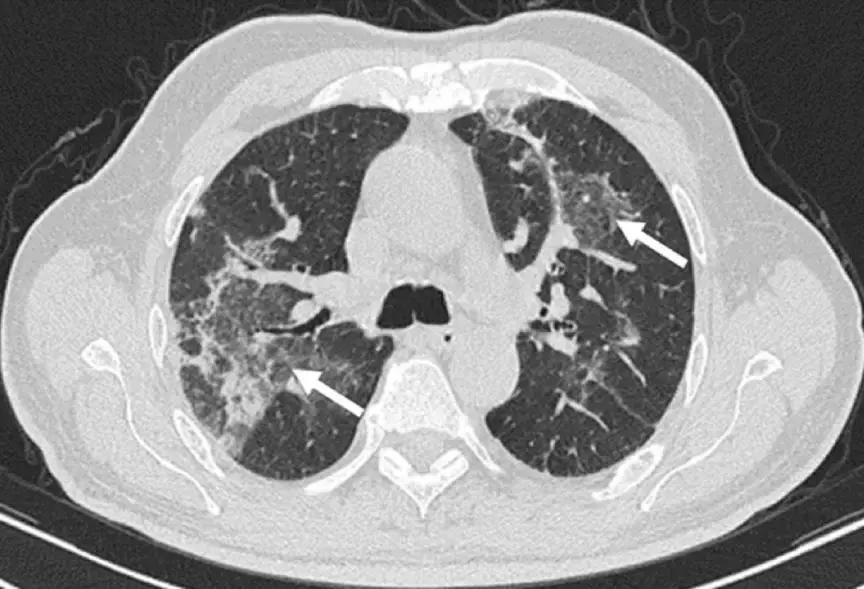

2、影像学是诊断线索

OP的影像表现:实变(周围、沿支气管血管束):80~95%;磨玻璃影:60~90%;小叶间隔增厚:55%;「反晕征」:20%;结节或团块:15~50%;还有「游走性」的特点。

实变:

中心型

混合型

磨玻璃影:

GGO合并带状实变

GGO,合并周围型及带状实变

小叶间隔增厚:

小叶间隔增厚,伴中心型实变、GGO